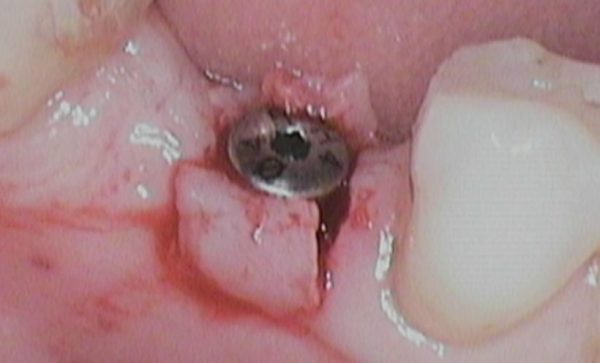

I have been a patient of Dr Verma for 8 years, my treatment has included crowns and an implant. Treatment plans and options are explained to me clearly, my concerns and anxieties are allieviated without hurry or pressure in a gentle and reassuring way. I feel my patient satisfaction is valued.

Sukal has been my dentist for many years, from simple check ups to a dental implant! I have always felt comfortable in the dentist chair and happily watched the TV on the ceiling while work is done on my teeth and never once felt any pain and always felt comfortable. I would never go anywhere else! Thank you all for being kind, caring and helpful at all times :-) Sarah Galloway